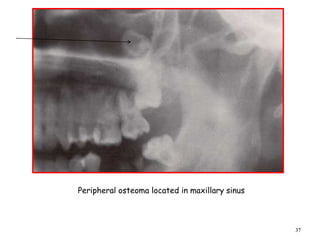

Peripheral osteoma located in maxillary sinus

A panoramic radiograph shows an osteoma

in the right mandibular angle region